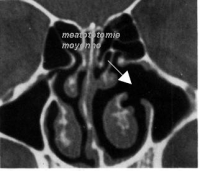

Méatotomie moyenne

La méatotomie moyenne est l’élargissement du canal naturel faisant communiquer le sinus maxillaire avec la cavité nasale.